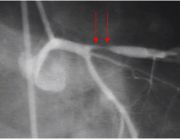

| 00:12, 15 October 2006 | Xray.jpg (file) |  |

28 KB | 1 | ||